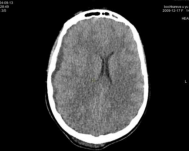

Figure 3: MSCT of the brain from 09/13/2024. Displacement of midline structures to the left. MSCT signs of subdural hygroma in the frontal-parietal-temporal region on the right. Suspected subarachnoid hemorrhage, with the presence of a hyperdense component in the frontal region on the right.

In the series of MSCT images Fig. 3, Fig. 4, Fig. 5, a shift of the midline structures of the brain to the left is visible, in Fig. 6, no shift of the midline structures of the brain is noted.